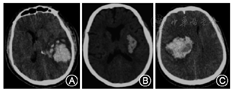

NCCT的优点为扫描速度快、检查时间短、不受金属器械等影响,可确定出血部位,估计出血量,判定出血是否破入脑室,并判断有无脑疝形成。

NCCT是临床确诊急性脑出血的首选方法,是脑出血检测的"金标准"。NCCT用于脑血管病的辅助检查需要注意以下几点:(1)对于急诊疑似脑卒中患者首选NCCT,可以明确患者是否有脑出血或蛛网膜下腔出血(subarachnoid hemorrhage,SAH),病灶呈现高密度影,为临床进一步诊治提供重要信息。在疾病的恢复期和慢性期,CT呈低密度影。(2)对疑似SAH患者,首选头颅CT检查。螺旋CT检测的阳性率可达98%~100%。但需要考虑就诊时间,发病24 h后,阳性率开始递减,出血5 d后,阳性率只有50%。SAH患者需要进一步行CTA/DSA以排除动脉瘤。(3)对脑出血患者,NCCT可以提示早期血肿扩大的征象(图1),目前大家比较认同的几个征象为:岛征、黑洞征、混合征、血肿内低密度、血肿边缘不规则和混合密度征,其预测血肿扩大的敏感度、特异度不完全相同[4]。岛征预测血肿扩大的敏感度、特异度分别为44.7%、98.2%[5];黑洞征预测的敏感度、特异度分别为39.3%、95.5%[6,7];混合征预测的敏感度、特异度分别为39.3%、95.5%[8]。(4)对于缺血性脑卒中患者,早期行NCCT的敏感度并不高,一般在发病24 h后,缺血性病灶才开始明显,表现为低密度改变;但早期可见大脑中动脉高密度征,预测大动脉闭塞的敏感度为67%,特异度为82%[9]。陈旧性缺血性脑卒中患者头颅NCCT低密度病灶需要与陈旧性脑出血低病灶相鉴别(图2),后者在T2WI表现为低密度病灶周边低信号环,系含铁血黄素沉积所致。